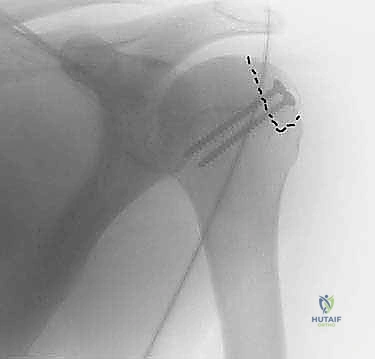

2. التصوير بالأشعة السينية (X-Rays)

تُعد الخطوة الأولى لاستبعاد الكسور الكبيرة الأخرى. يتم أخذ وضعيات خاصة (مثل وضعية Stryker Notch أو AP بوضعية الدوران الداخلي) لإظهار الانخساف العظمي في رأس العضد بوضوح.

يتم تنظيف موقع آفة هيل ساكس من الأنسجة الليفية للوصول إلى عظم حي ينزف، مما يحفز عملية الالتئام. بعد ذلك، يتم إدخال الطعم العظمي المُشكل في مكانه.

يستخدم الدكتور هطيف براغي طبية خاصة (غالباً براغي التيتانيوم المجوفة أو البراغي القابلة للامتصاص) لتثبيت الطعم بقوة فائقة في رأس عظم العضد. يتم غرس رؤوس البراغي تحت مستوى سطح الغضروف لضمان عدم احتكاكها بالجوف الحقاني أثناء حركة الكتف.